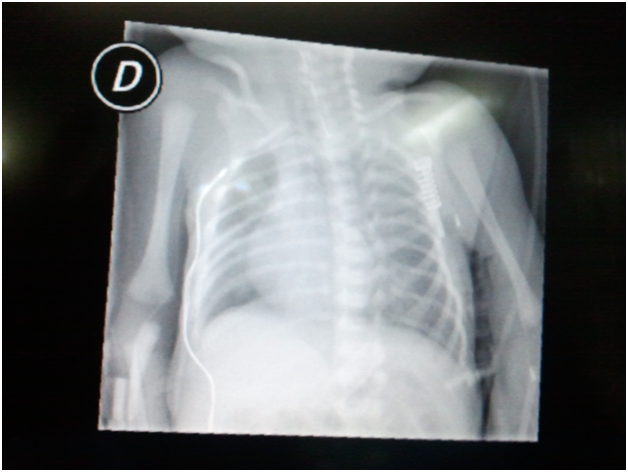

Hemodynamically, our patient required dopamine doses of 5mcg/kg/min during the repair stage of the esophageal atresia (about one hour), probably because of the venous return decrease caused by the pulmonary collapse done with the surgical valve. The infant remained hemodynamically stable, which made possible to stop dopamine doses at the end of surgery. It was not necessary neither blood transfusion nor other drugs to maintain homeostasis. The patient temperature ranged between 35.5 and 36.5ºC thanks to surgical warming blanket and warm fluid therapy support. As far as surgical technique is concerned, in first place, fistula resection was performed without incident and with satisfactory result, followed by the esophageal atresia correction. In fact, sutures were tested in the OR using Valsava maneuver made with sporadic manual ventilation (Figures 1 & 2).

Figure 1 Chest X-ray, prior to surgical intervention.